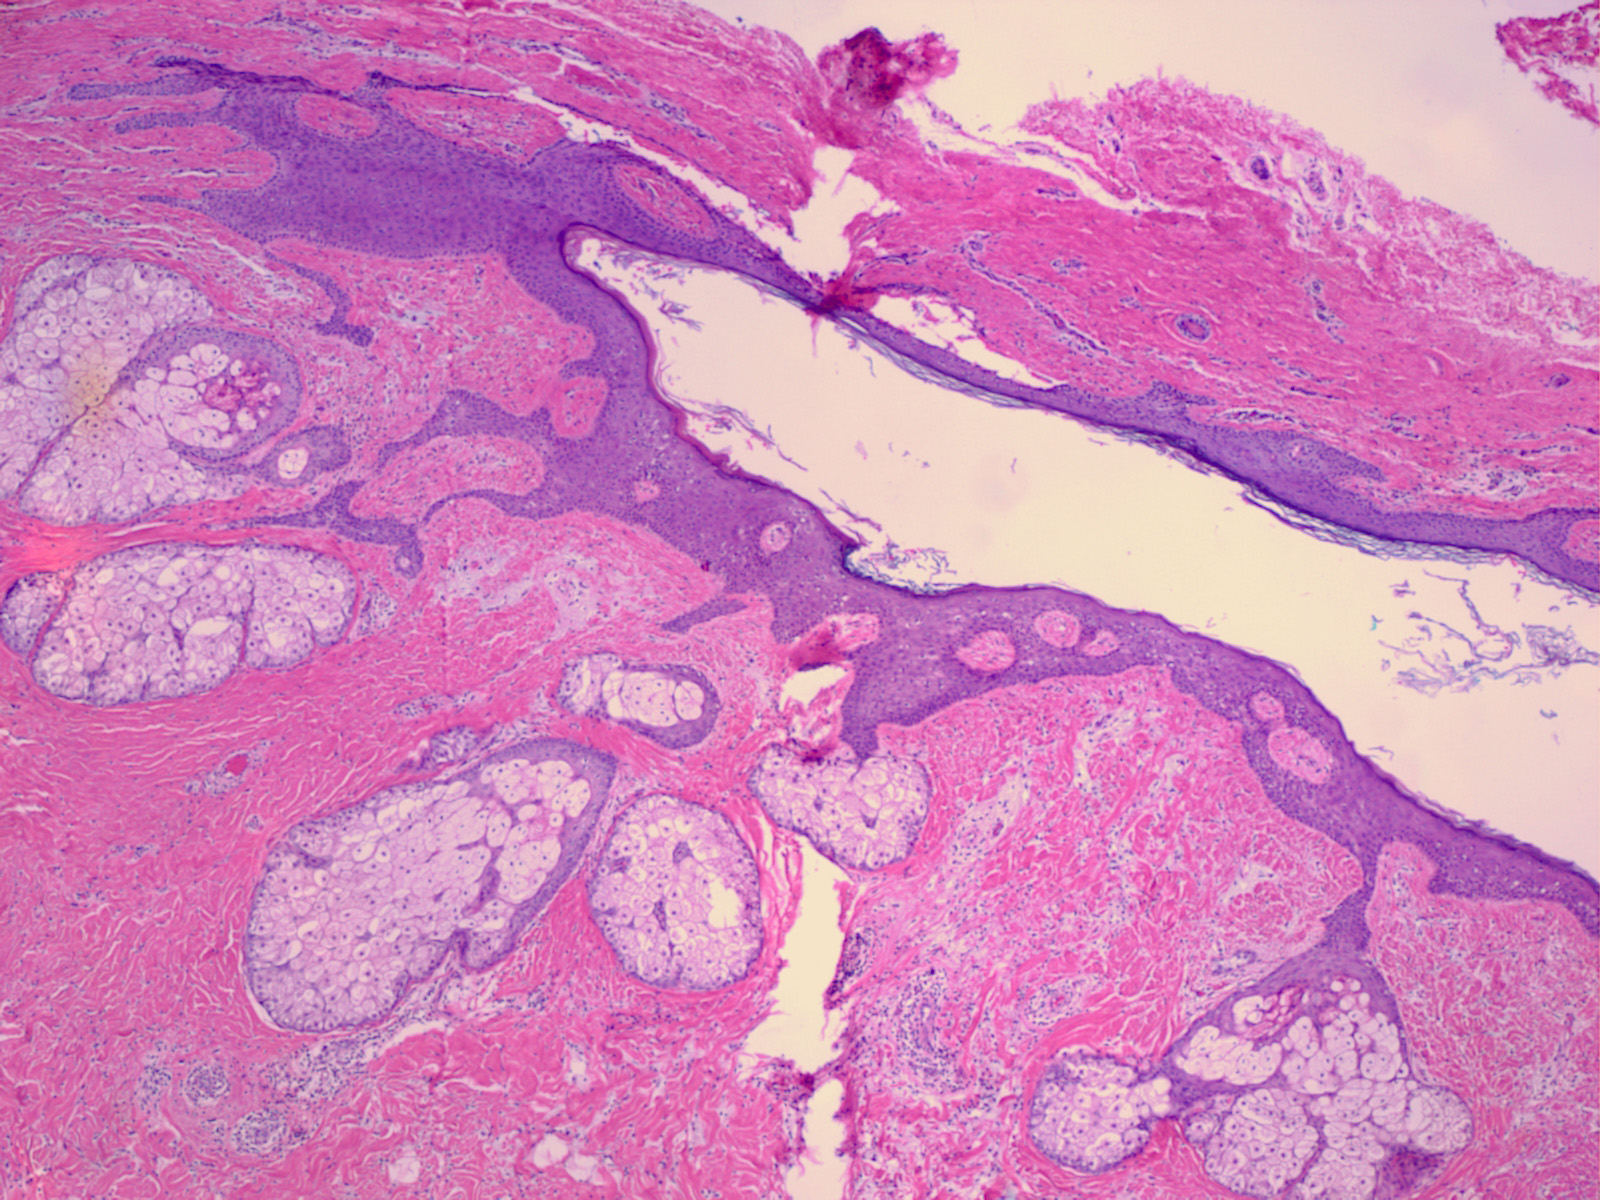

Histopathology. Dermoid cysts, in contrast to epidermal cysts, are lined by an epidermis that possesses various epidermal appendages that are usually fully matured . Hair follicles containing hairs that project into the lumen of the cyst are often present. In addition, the dermis of dermoid cysts usually contains sebaceous glands, often eccrine glands, ——–,. |